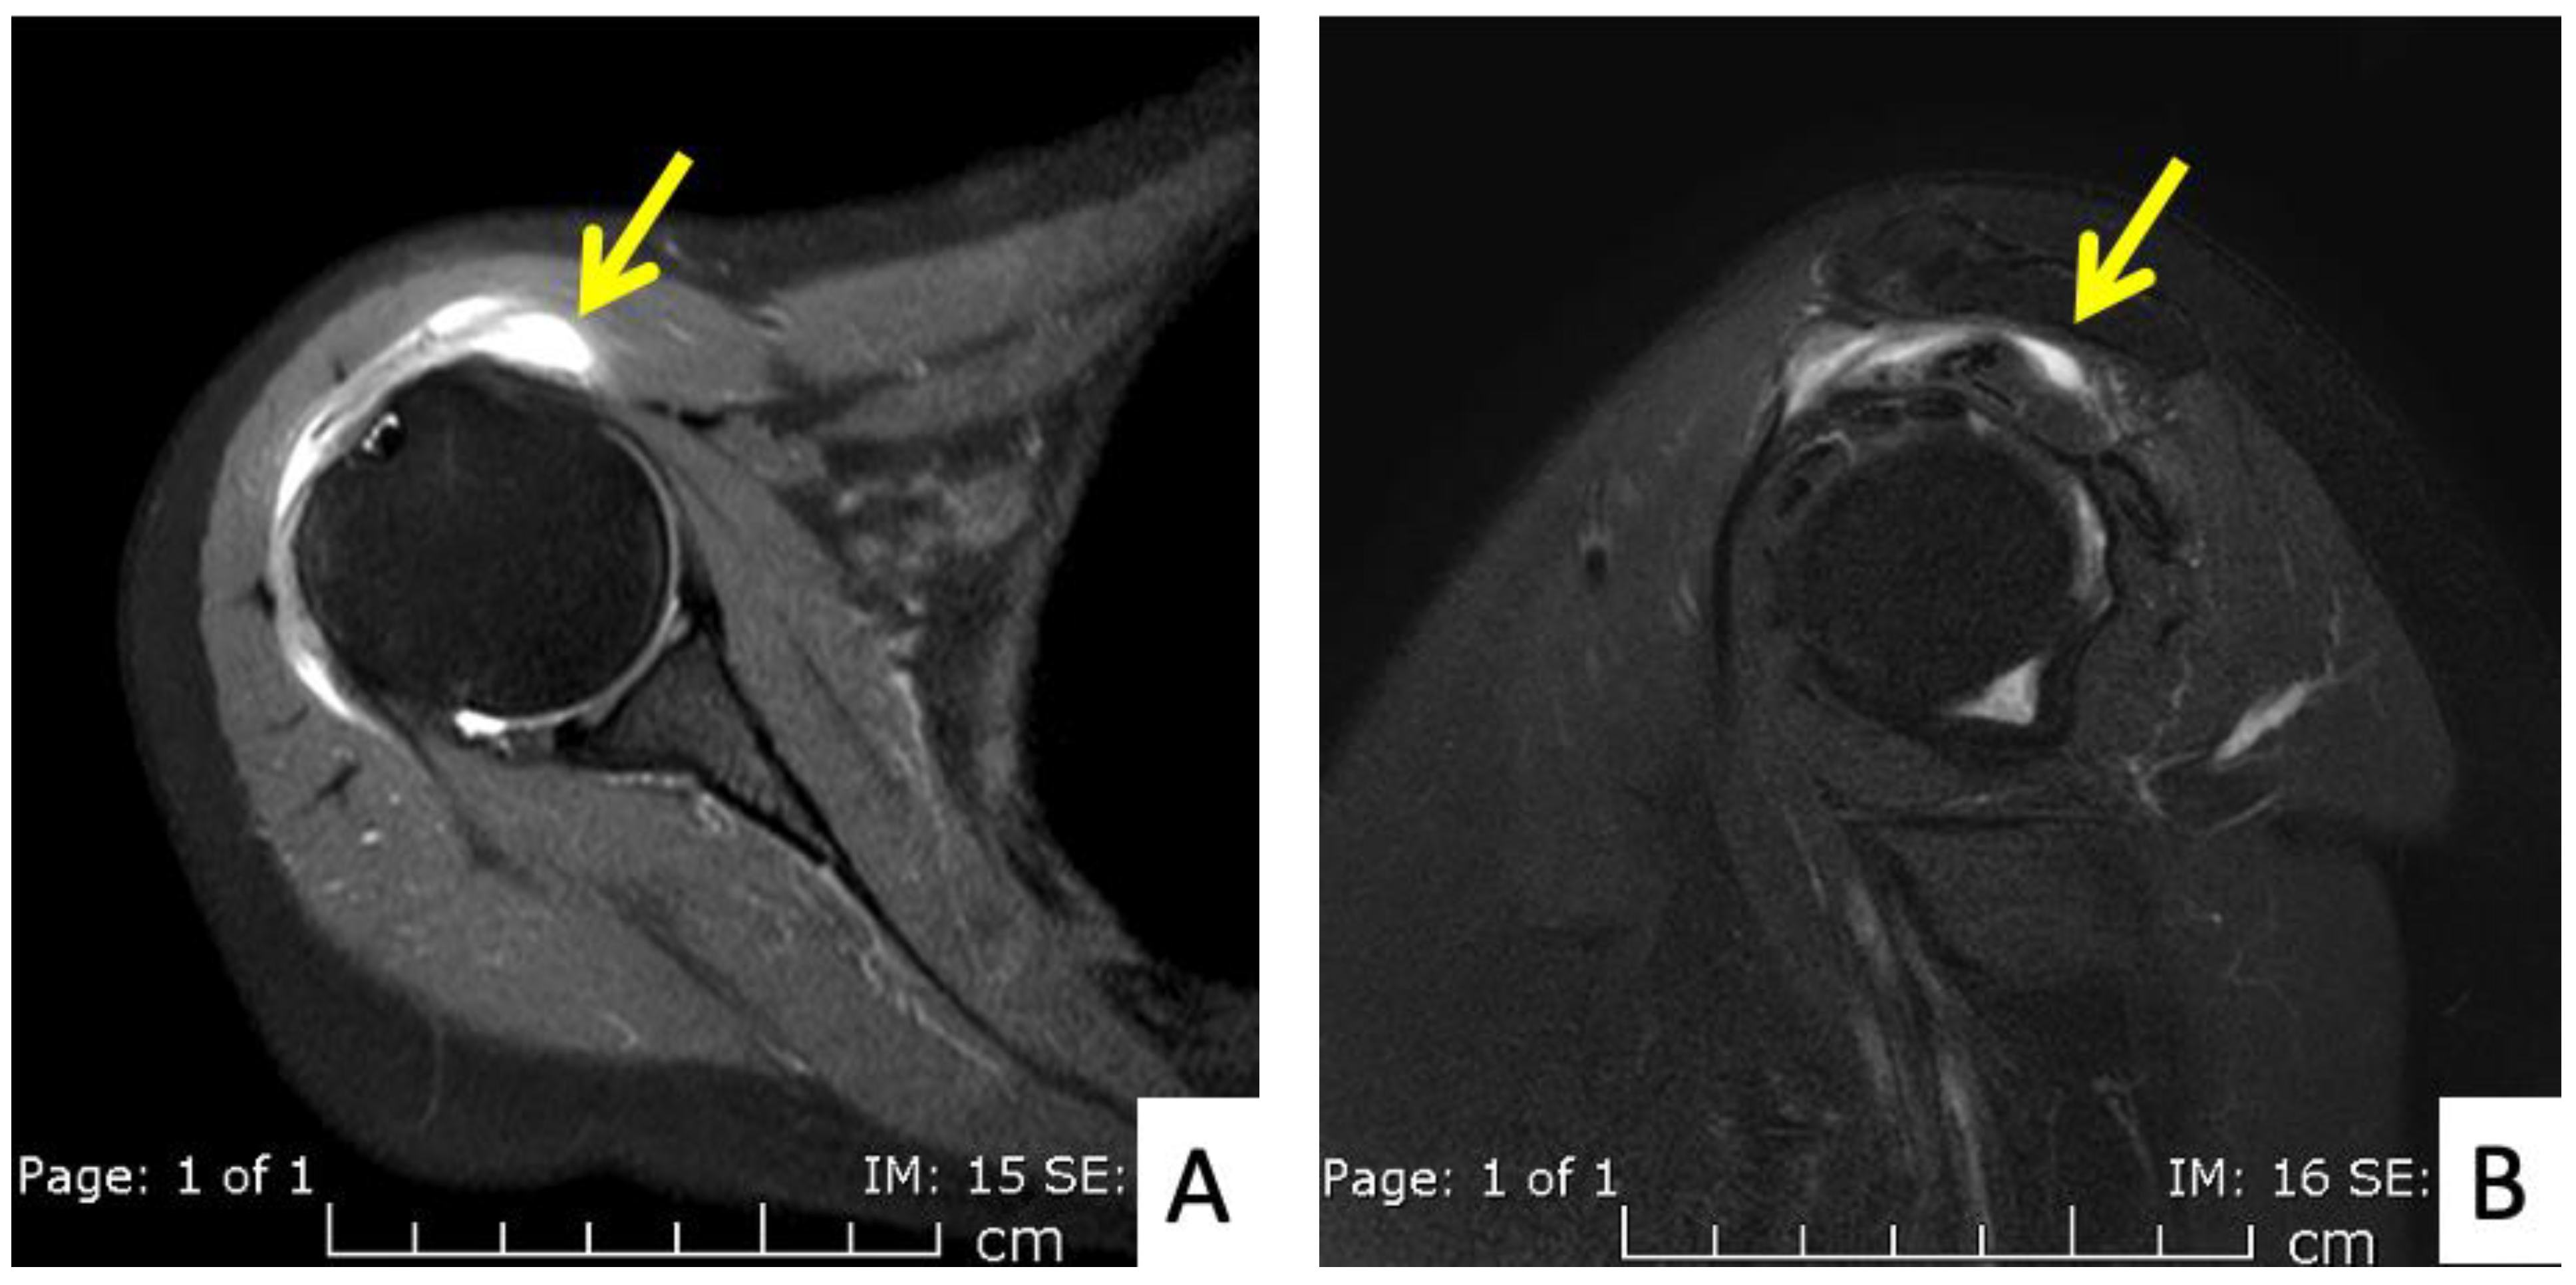

Figure 3.

MRI images of the right shoulder of Patient 1; proton density-weighted images in (A) axial and (B) sagittal views reveal a large amount of fluid in the subdeltoid bursa (yellow arrow). The images also reveal additional subscapularis tendinosis and chondromalacia of the glenohumeral joint, indicating background osteoarthritis.